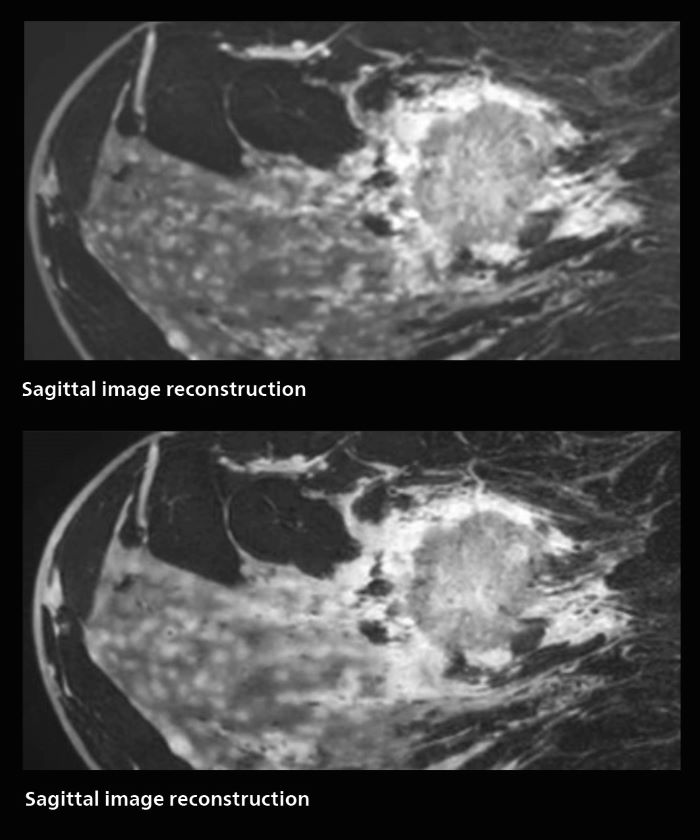

3D MRI of breast cancer

Scanning was performed with two different voxel sizes. AI enabled volume MRI allows image reconstruction in other directions. Biopsy revealed invasive ductal carcinoma in this patient. Performed on Elition X.

Fast AI-enabled MRI of breast cancer: comparing 3D acquisitions with 0.75 mm and 0.6 mm isotropic voxels.

Fast, dynamic breast imaging for diagnostic confidence

Speed and high image quality are also important factors determining the diagnostic value of breast MRI. “When the spatial resolution is not high enough for making the diagnosis of breast cancer, a very difficult decision must be made,” says Dr. Katahira. “Since SmartSpeed now allows us to increase the resolution, we can often easily provide a confident answer. In the past with SENSE we used 1.2 mm isotropic voxels in breast imaging after contrast admission. With Compressed SENSE that is 0.8 mm. Now with SmartSpeed we can acquire 0.6 mm isotropic voxels and the images are so clear that even tiny details are clearly visible.”

“For example, we can now scan 20 consecutive, very fast dynamic images of the mammary glands with a single 3-second volume acquisition. This allows us to see how the blood flow is progressing in a very different way.”

“The use of SmartSpeed has considerably improved our breast cancer imaging, with higher temporal resolution, higher spatial resolution, and higher SNR compared to the past, when we were using just Compressed SENSE. In addition, the dynamic study is now more useful in diagnosis because the ultrafast dynamic scan can be taken every 3 seconds.”